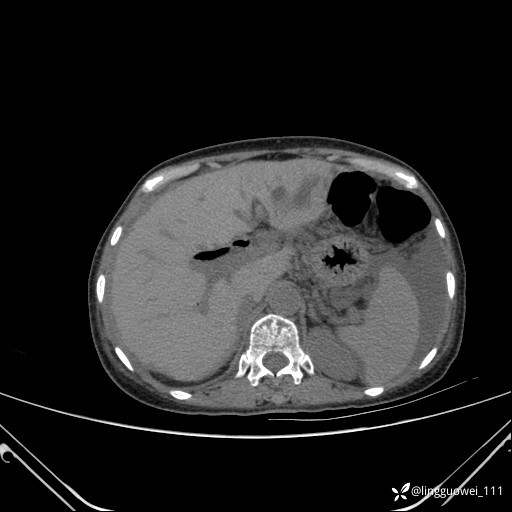

病例女,65岁,门诊行胃肠镜检查后,说腹胀入院检查,CT能发现病因吗?已公布结果

主诉:门诊行胃肠镜检查后,诉腹胀,入院检查,肝有病变吗?腹膜及腹腔的表现有特征性吗?

门脉期: